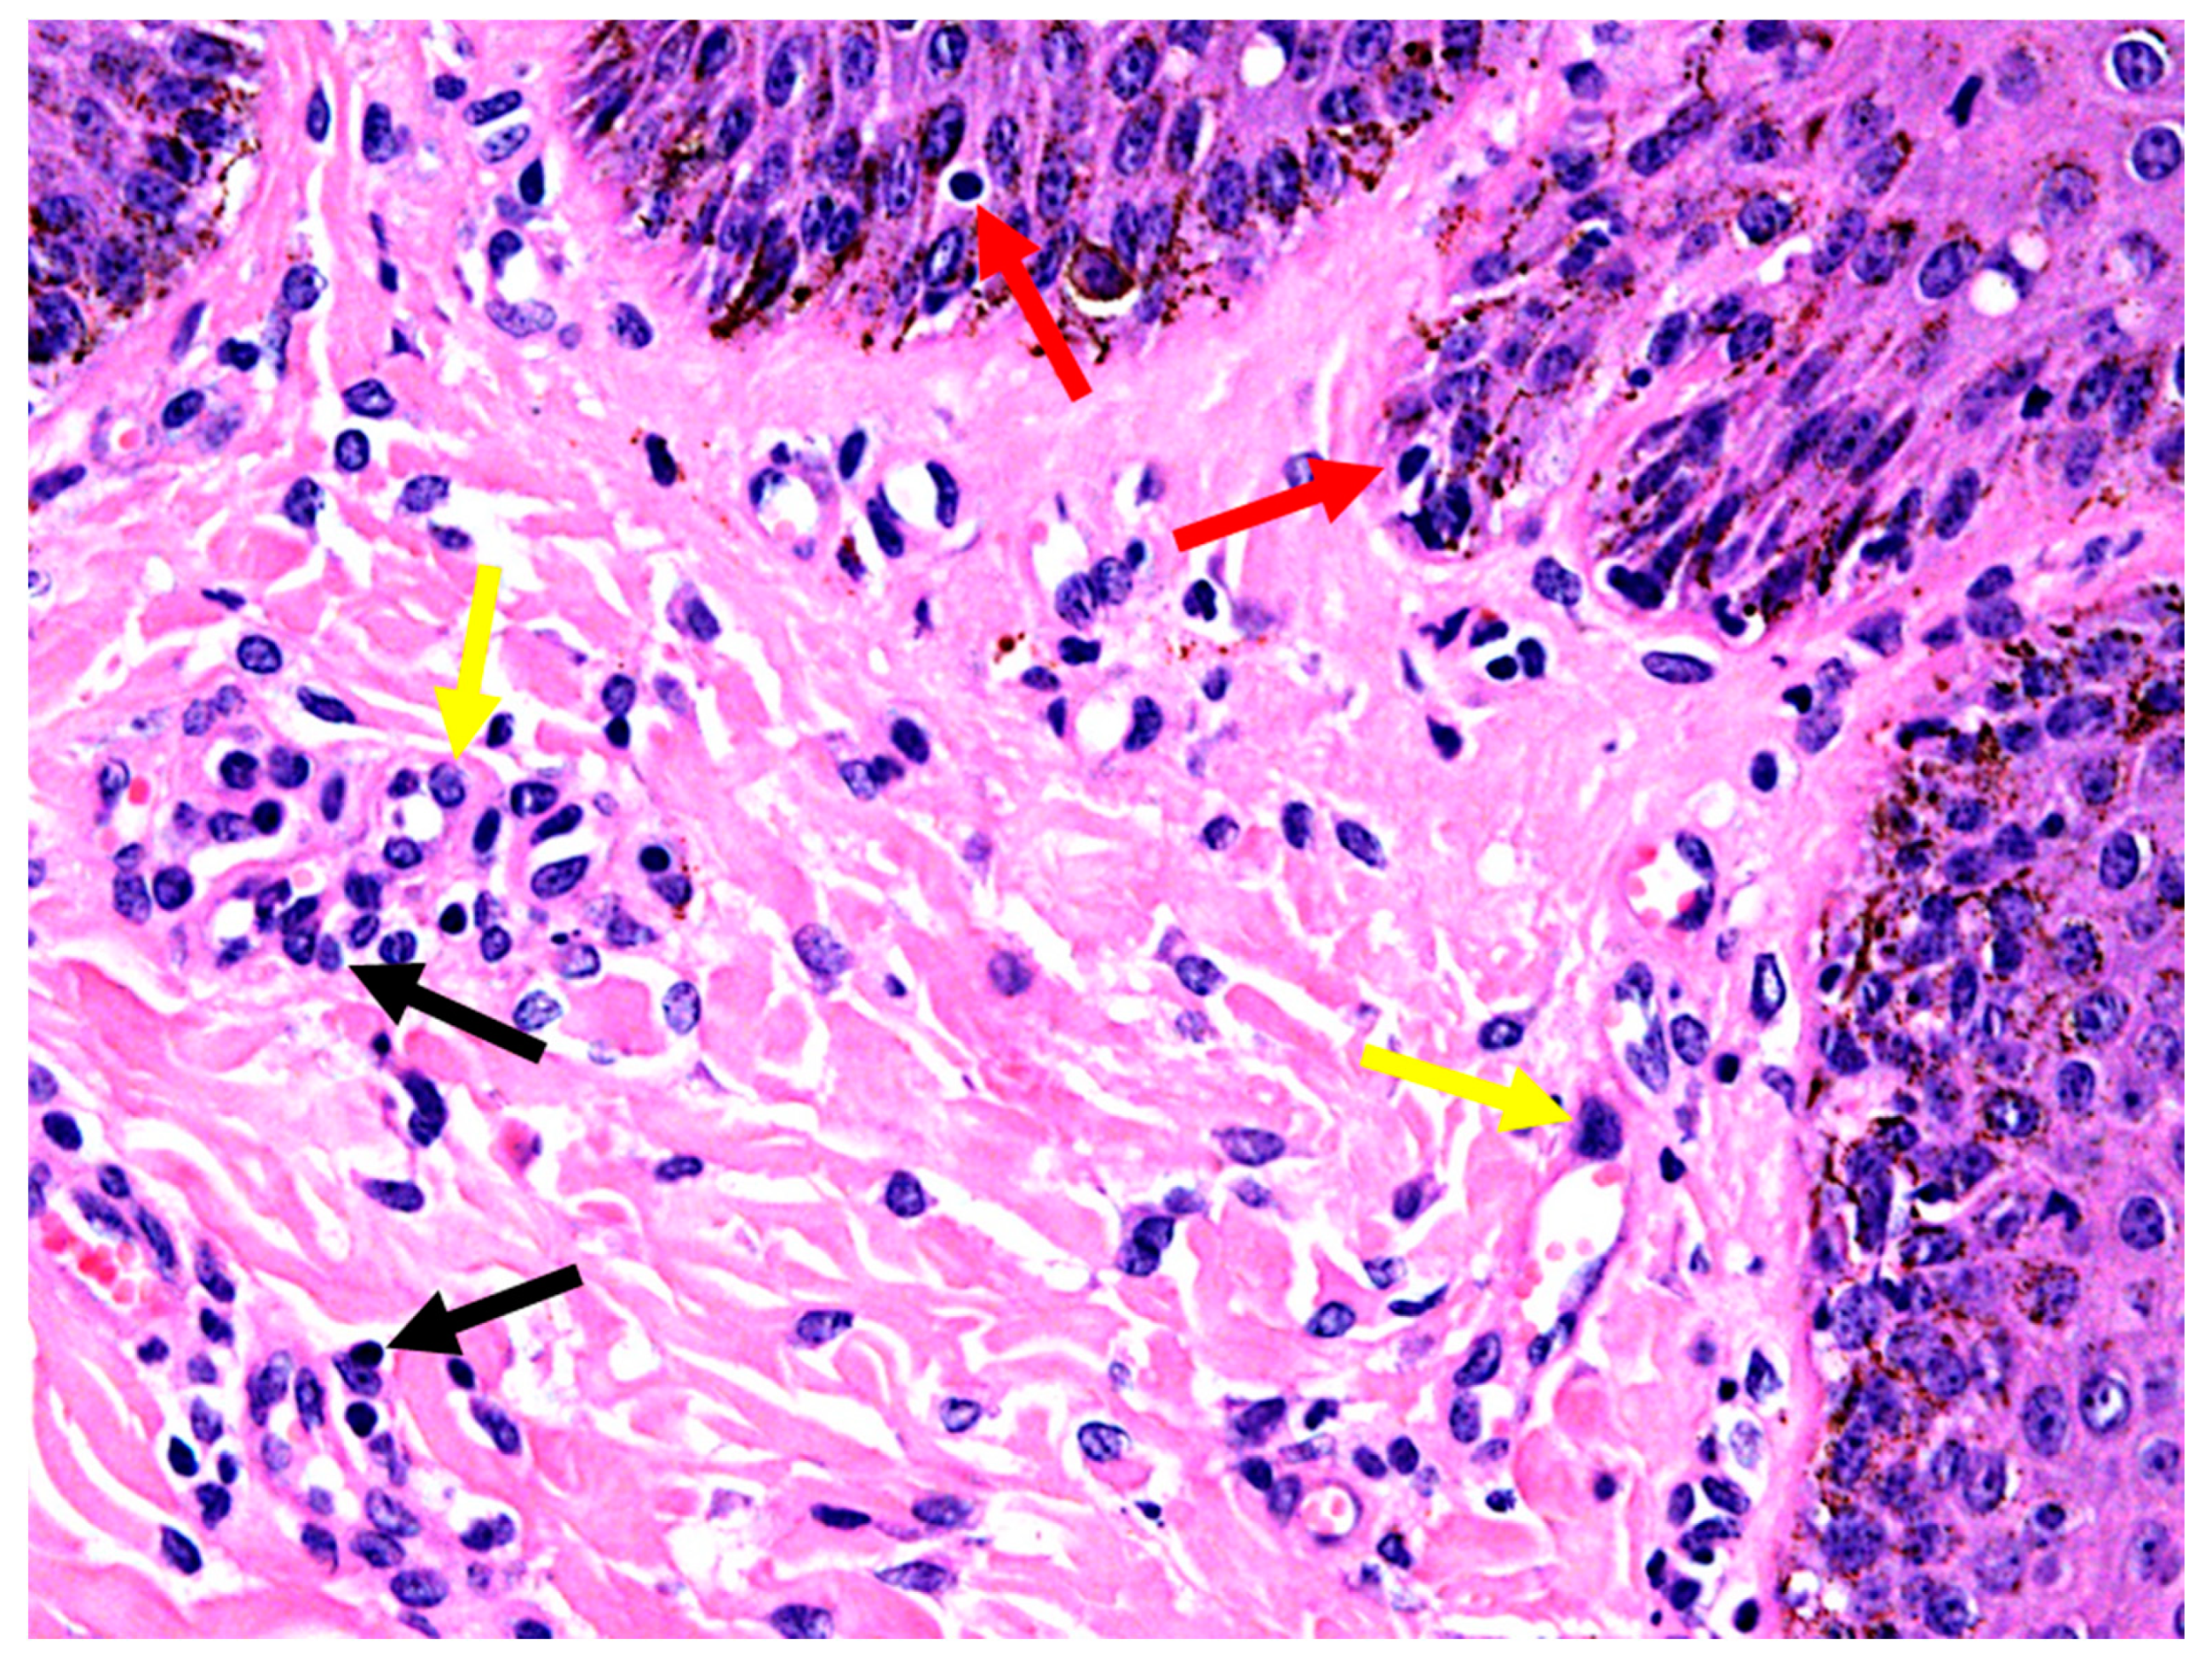

3.4. Histopathology

3.5. Histopathological Diagnosis